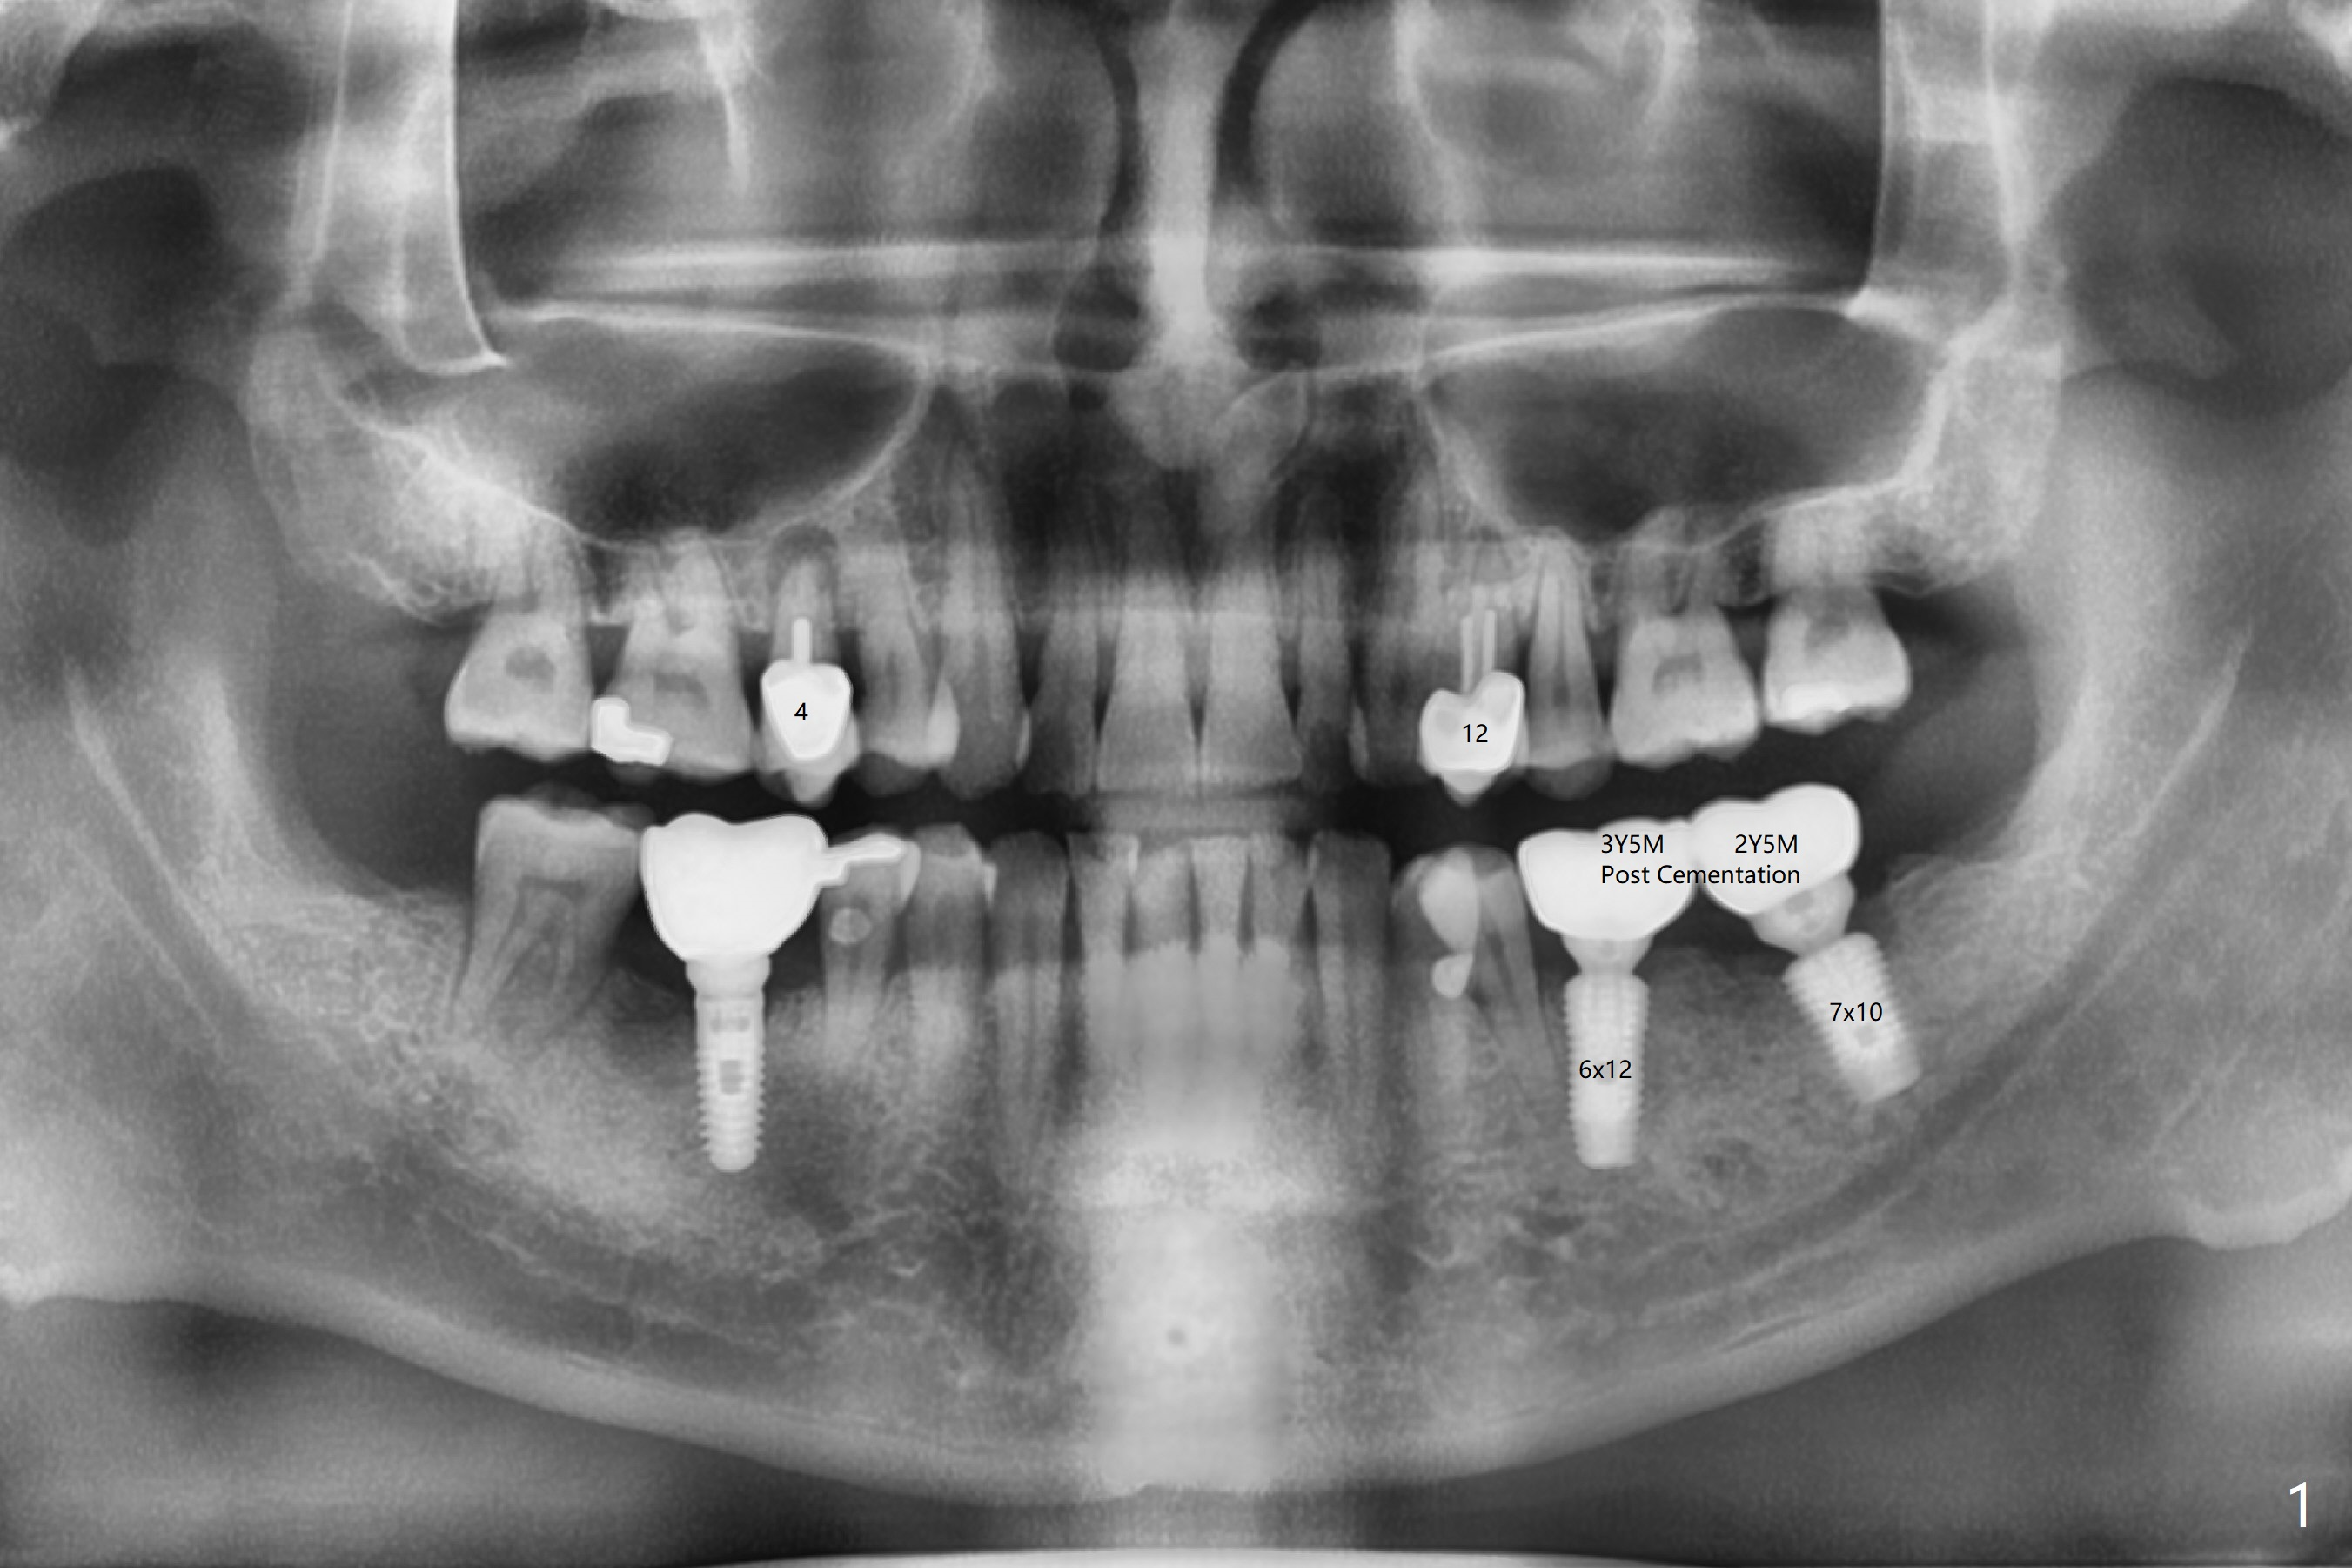

A 54-year-old man with bruxism requests treatment at #4 and 12 with buccal fistulae (Fig.1-3). Due to large defects, a large, but short implants (5x7.3 mm) will be used for primary stability. PRF membranes (x4) and liquid (x1 for sticky bone) will be prepared for sinus lift and buccal defect repair. Guided surgery will be utilized to prevent poor trajectory at #18 and 19 (Fig.1). The result turns out to be good (Fig.4).